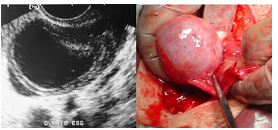

Paciente do sexo feminino com dor importante e incapacitante no baixo ventre de início súbito. Realizou exame ultrassonográfico que demonstrou:

Baseado nas imagens disponibilizadas, qual o seu diagnóstico?